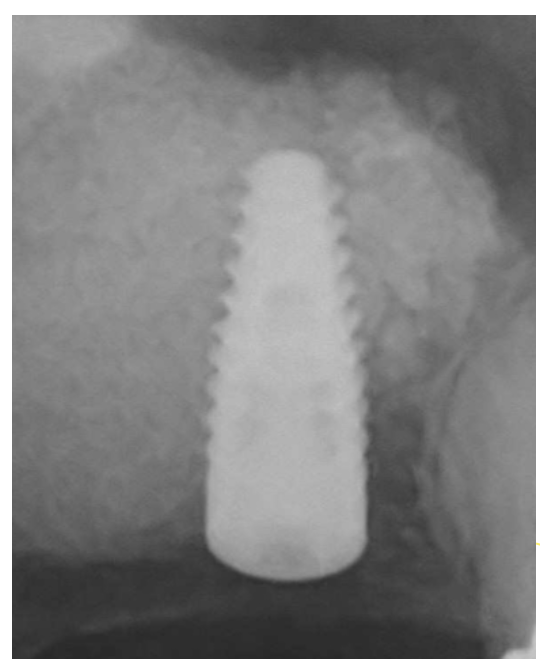

右上奥歯にインプラントを希望して来院されました。他院では骨がないためインプラントは出来ないと言われたとのことでしたが、サイナスリフト(上顎洞底挙上術)を行うことで骨の高さが3mmから14mmまで増加しました。

治療回数:サイナスリフトは一度の手術で終わります。その後インプラントの手術が必要になります。

治療期間:サイナスリフトを行いしっかりした骨が出来るのは約6ヶ月かかります。その後にインプラント治療を行います。

サイナスリフト:¥200,000(税込220,000)

上顎洞底の粘膜を持ち上げて、そこに骨を作る手術になります。粘膜は1mm程度の薄い膜のため持ち上げる際に穿孔(穴が開く)する場合があります。小さい穴であれば閉鎖することが出来ますが、大きな穴が開くと再度手術になる場合があります。術後に腫れ、痛み、出血、感染のリスクがあります。